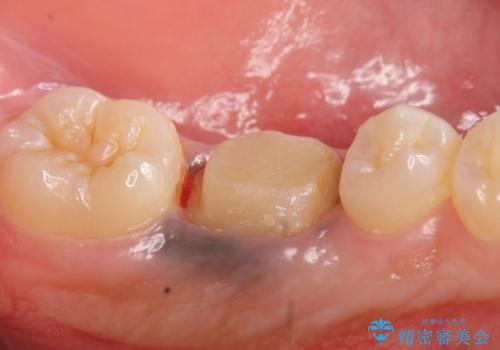

- 他院にて治療途中の歯を診て欲しいといらっしゃった方の症例です。

X線上で根尖病変を認めたため再根管治療を行い、オールセラミッククラウンによる補綴を行いました。